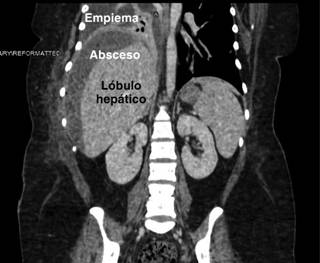

Con respecto a los estudios de imagen el tamaño promedio fue de 4.4 ± 5.2. En la localización, 18 (75%) de los abscesos ocurrieron en el lóbulo derecho y 6 (25%) en ambos lóbulos. Con 20 (83%) pacientes con un solo absceso y el resto con dos o más abscesos. No se reportó pared engrosada, septos, neumobilia o rotura del absceso en ninguno de estos casos.

El tratamiento y el posoperatorio se describen en la Tabla 2. A todos los pacientes se les colocó sonda de toracostomía para drenaje del empiema (Figura 1), reportando 24 (100%) de empiema localizado del lado derecho y 4 (16%) ambos lados. De los 14 (58%) pacientes sometidos a toracoscopia, 12 (50%) fueron egresados sin sonda pleural. Los restantes 10 pacientes fueron egresados con sonda pleural. Se reportaron 2 (8%) mortalidades.